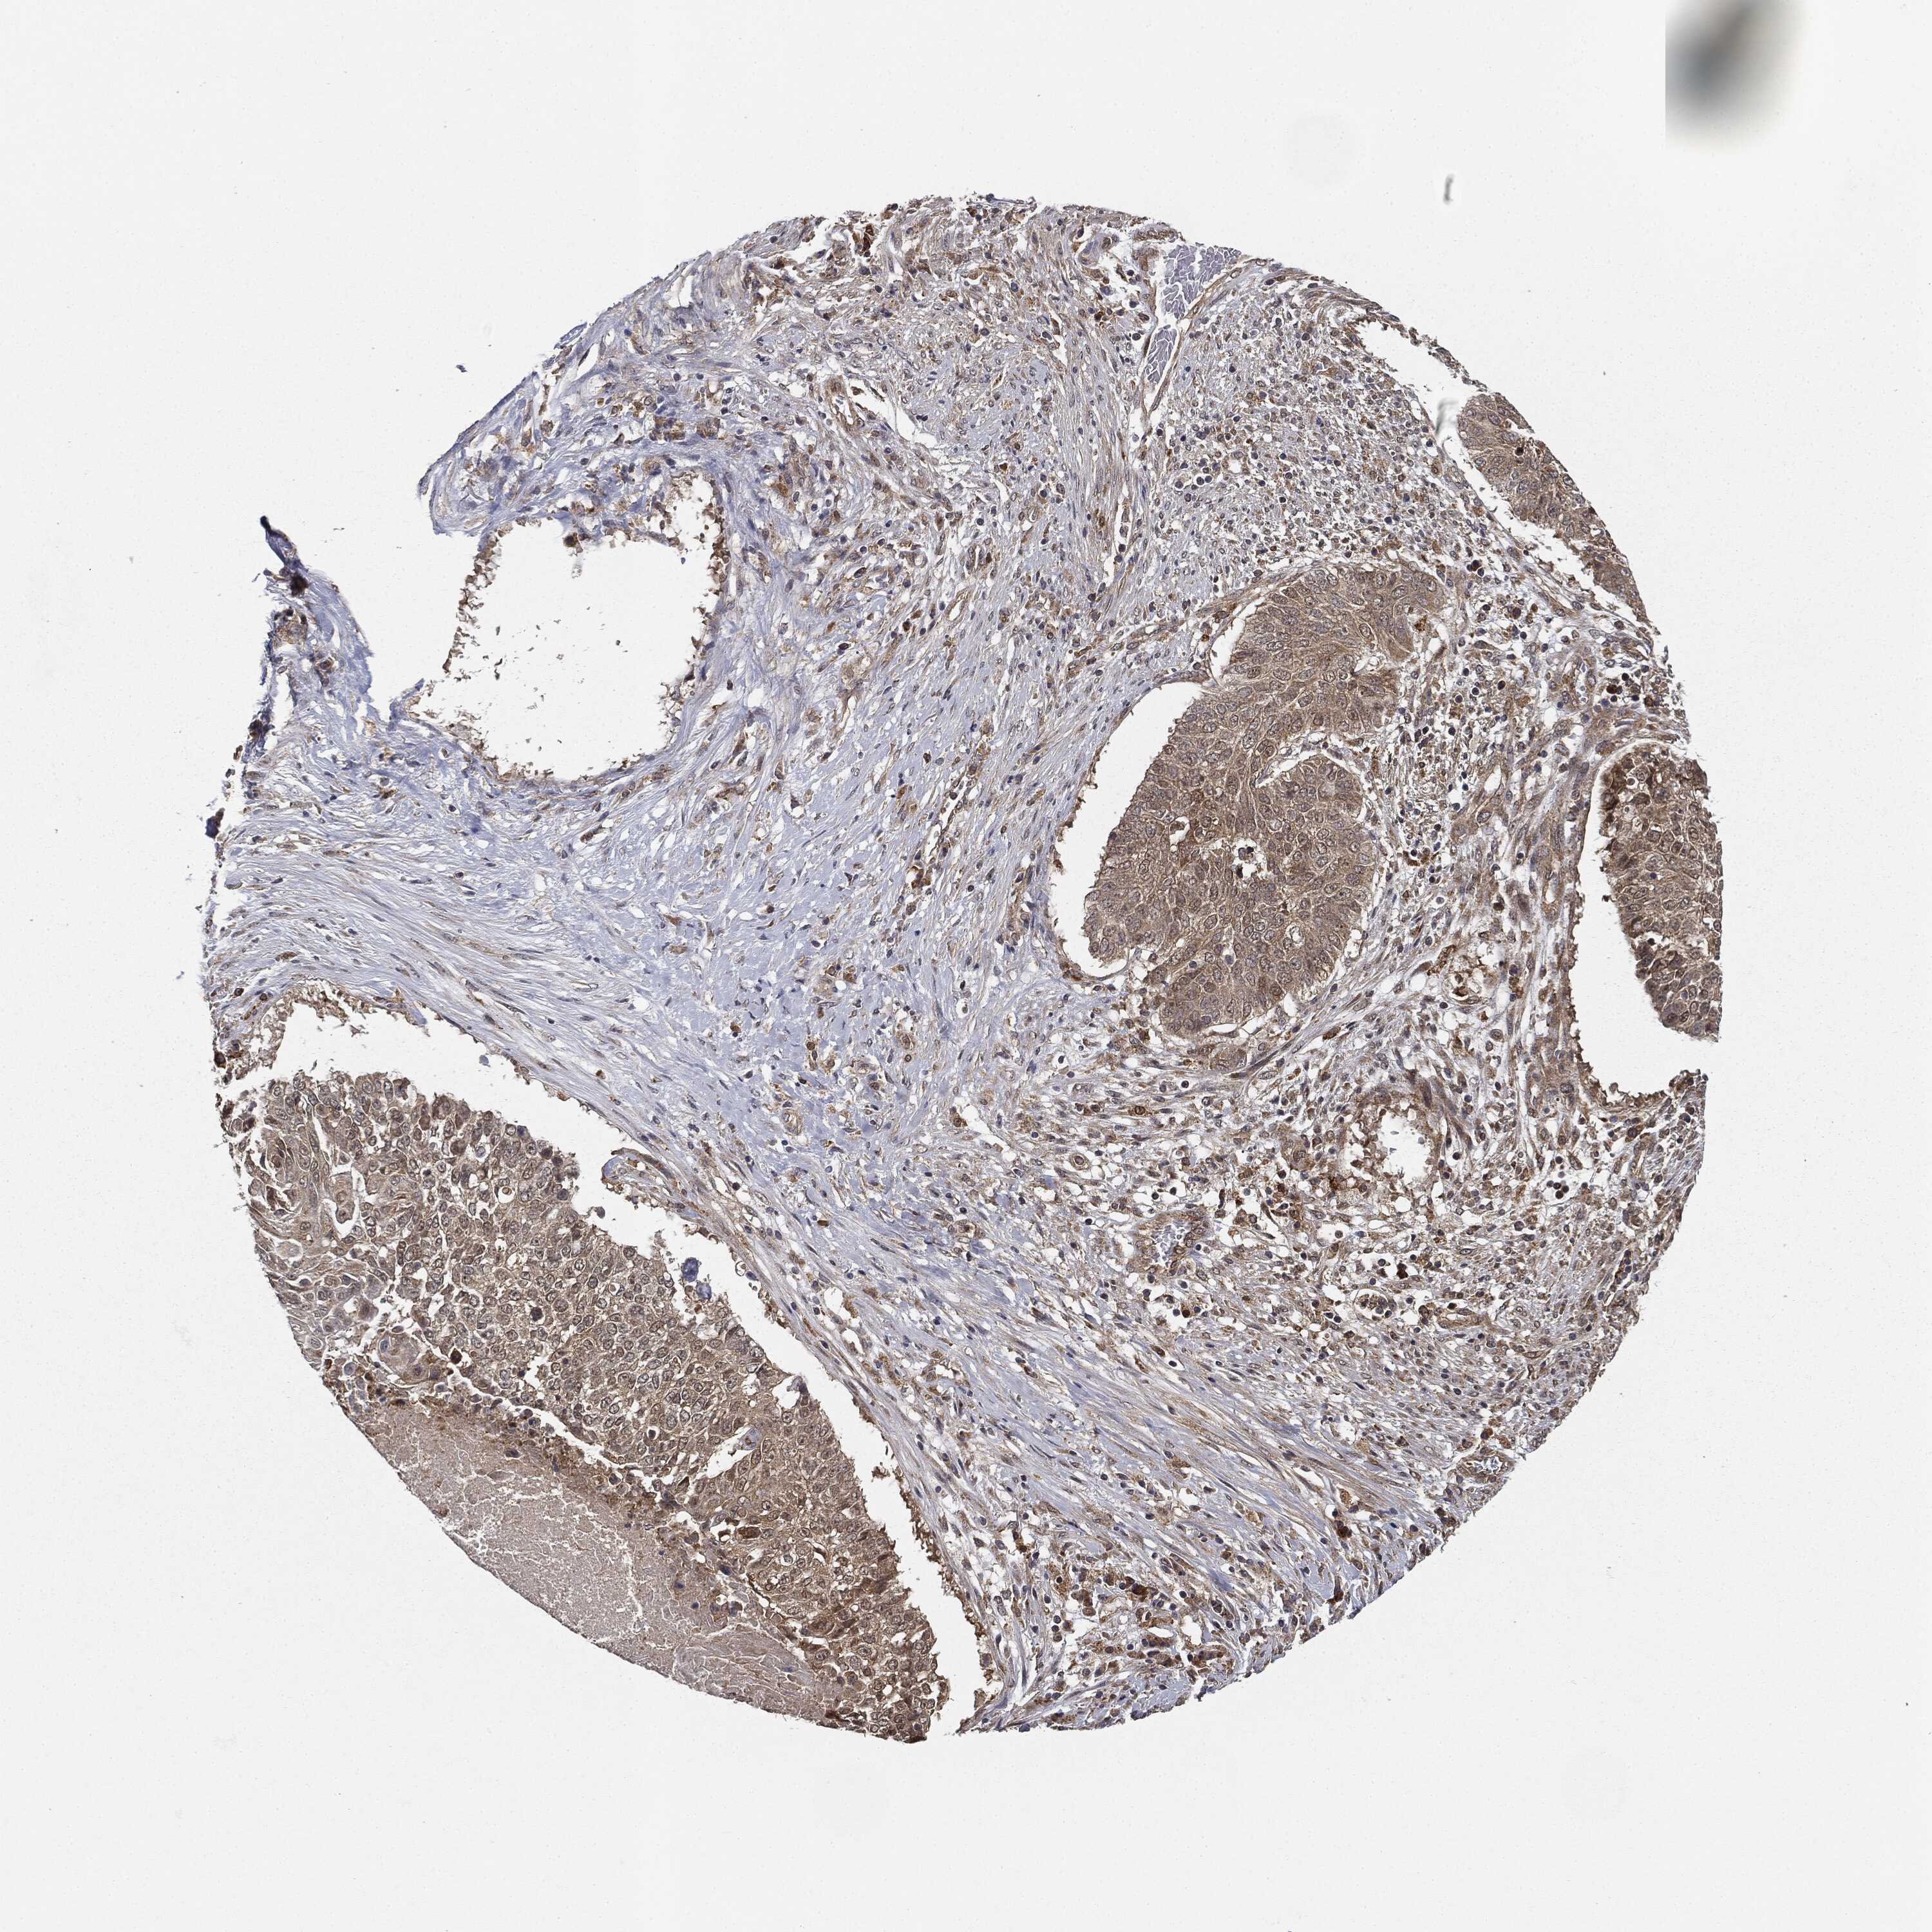

CANCER LUNG CANCER Show tissue menu

LUAD TCGA LUAD VALIDATION LUSC TCGA LUSC VALIDATION PROTEIN LUAD CPTAC PROTEIN LUSC CPTAC PROTEIN EXPRESSION

ANTIBODIES

AND

VALIDATION